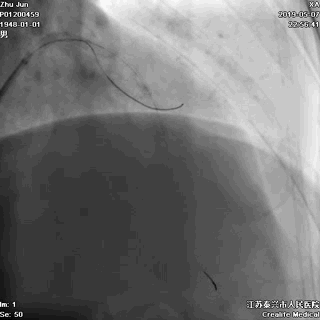

五、高压后扩张

---保证STENT充分贴壁

非顺应性球囊高压后扩,保证STENT充分贴壁

六、主干支架近段优化

---不能省略的步骤

大一号球囊高压扩张近段STENT

七、最终结果

---即刻效果完美

手术即刻效果完美,患者存活